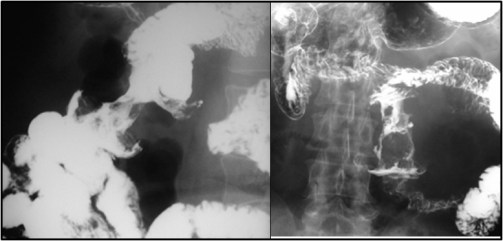

SIGNO DEL CORAZÓN DE MANZANA

Los tumores malignos del colon pueden producir una estenosis circunferencial con márgenes abruptos entre la zona de estrechamiento y la sana, cuyo aspecto, en el enema de bario, recuerda a una manzana mordisqueada. Este tipo de estenosis también se denomina «en servilletero».

El signo también puede verse en la TC, aunque en el enema es más reconocible y fue descrito en esta exploración.

Realmente no es un signo exclusivo del colon, aunque lo incluyamos en esta sección. Puede presentarse en el intestino delgado, aunque en más raras ocasiones. Las imágenes de abajo corresponden a un paciente que presenta el Signo del corazón de manzana por neoplasia maligna en yeyuno. Representa, como en el colon, un crecimiento del tumor que estenosa concéntricamente la luz intestinal.